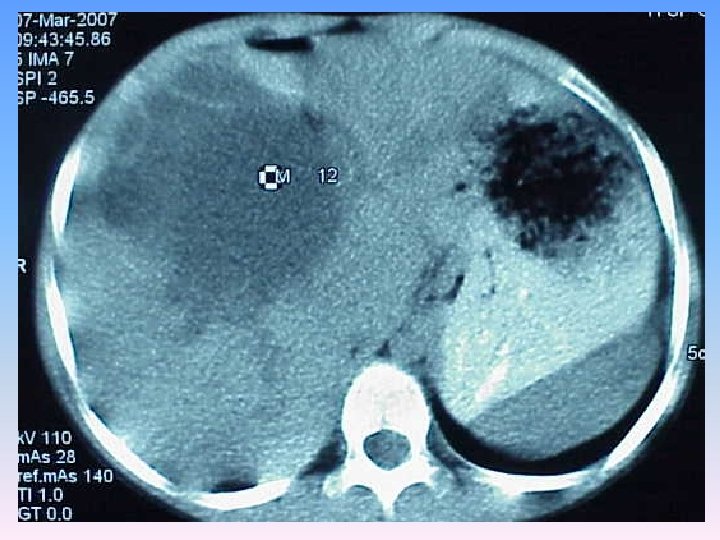

Abdominal CT Scan § A regular lobulated cystic mass in right lobe of liver (120 x 120) without calcification causing dilatation of intra & extra biliary ducts.

MRCP & MRI § Huge thicked wall cystic mass (140 x 120 mm), at the portahepatis that seems connected to biliary tree and gall bladder, resulted in severe dilatation of intra hepatic bile ducts and displaced right kidney posteriorly. § Spleen, kidneys, bowel loops and abdominal wall are normal. § Finding could be due to congenital anomalies like choledocal cyst, Duplication cyst, mesenteric cyst and hydatid cyst are in DDx.